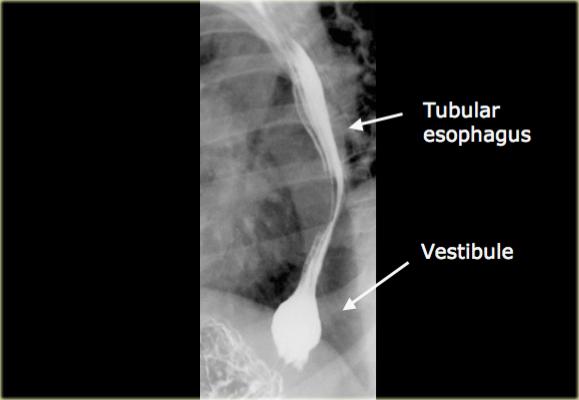

- Thực quản dạng ống kéo dài đến ngay trên cơ hoành.

- Sự giãn phình dạng bóng ở đoạn thực quản xa được gọi là tiền đình, tương ứng với cơ thắt thực quản dưới được xác định bằng đo áp lực.

Sự giãn phình này được thể hiện rõ nhất khi nín thở ở thì hít vào hoặc nghiệm pháp Valsalva.

Không nhầm lẫn hình ảnh này với thoát vị khe hoành.